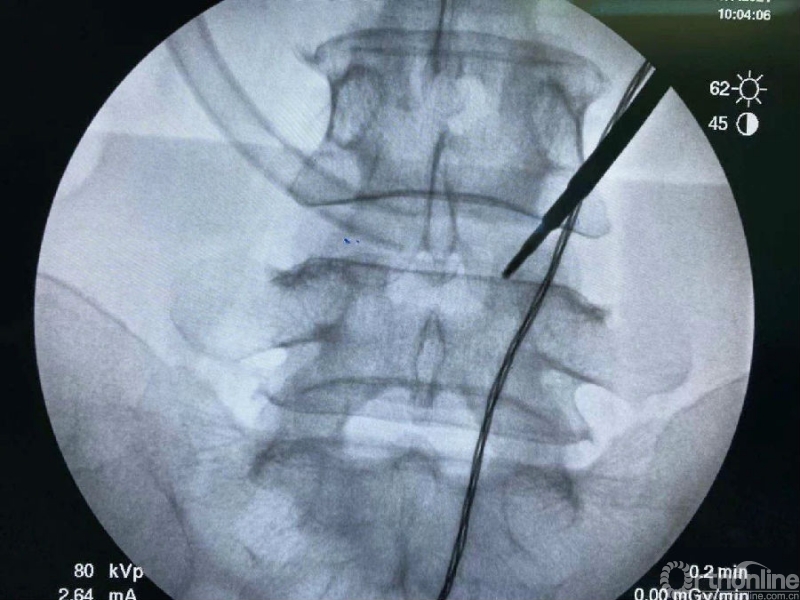

我们选用mark磨钻在下关节突上钻孔固定进行透视来确定关节突内缘磨除的外界。

定位磨钻细小,且可立于钻孔内进行透视定位。

术前克氏针确定内镜口位置位于椎板稍微偏远,是一个比较理想的定位。

然后建立通道。